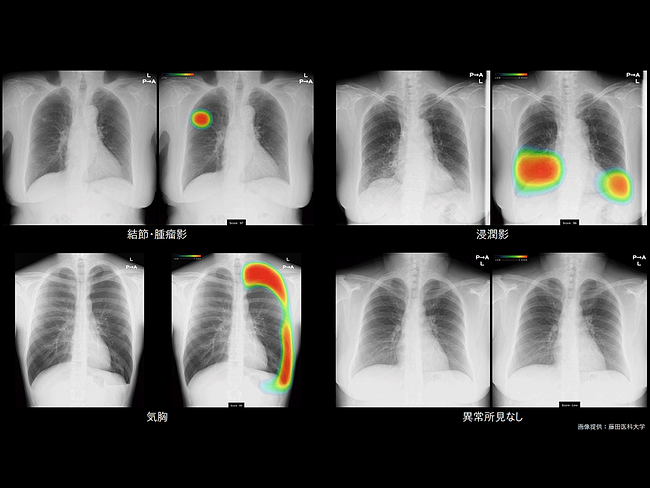

Chest X-ray analyzed using CXR-AID

Fujifilm, Lunit get nod for collaborative AI-powered chest X-ray analysis system in Japan

Aug. 20, 2021

By Gina Lee

Fujifilm Holdings Corp. has bagged the Japanese Pharmaceuticals and Medical Devices Agency (PMDA)’s approval for CXR-AID, its artificial intelligence (AI) powered chest X-ray analysis system developed in collaboration with Lunit Inc.